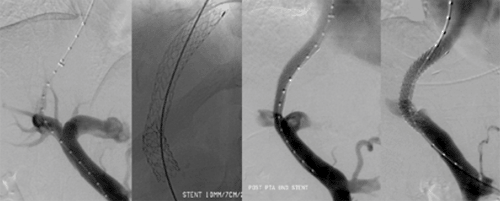

Alternativ zur offenen chirurgischen Therapie eines Aortenaneurysmas besteht die Möglichkeit einer endovaskulären Aneurysmaausschaltung mittels eines Stentgrafts (gewebeummanteltes Metallgittergeflecht). Voraussetzung für die endovaskuläre Therapie ist jedoch eine anatomische Eignung, welche eine ausreichende Weite der Beckengefäße und nötige Verankerungszonen für den Stentgraft mit sich bringt. Die Stentgraft Implantation wird von Interventionellen Radiologen in Zusammenarbeit mit Anästhesist:innen und Gefäßchirurg:innen durchgeführt. Der Eingriff erfolgt unter Spinalanästhesie oder einer Allgemeinnarkose. Der Zugang zum Aneurysma wird üblicherweise durch einen kurzen Schnitt in der Leiste geschaffen. Zur Darstellung des Aneurysmas wird zuerst eine Angiographie der Bauchaorta durchgeführt (Abb.2). Folglich wird unter Röntgendurchleuchtung der Stentgraft über einen Führungsdraht in die Bauchaorta eingebracht und unterhalb der Nierenarterien verankert. Eine Kontrollangiographie nach Stentgraft-Implantation wird zum Nachweis eines guten Ausschlusses des Aneurysmas durchgeführt (Abb.3).